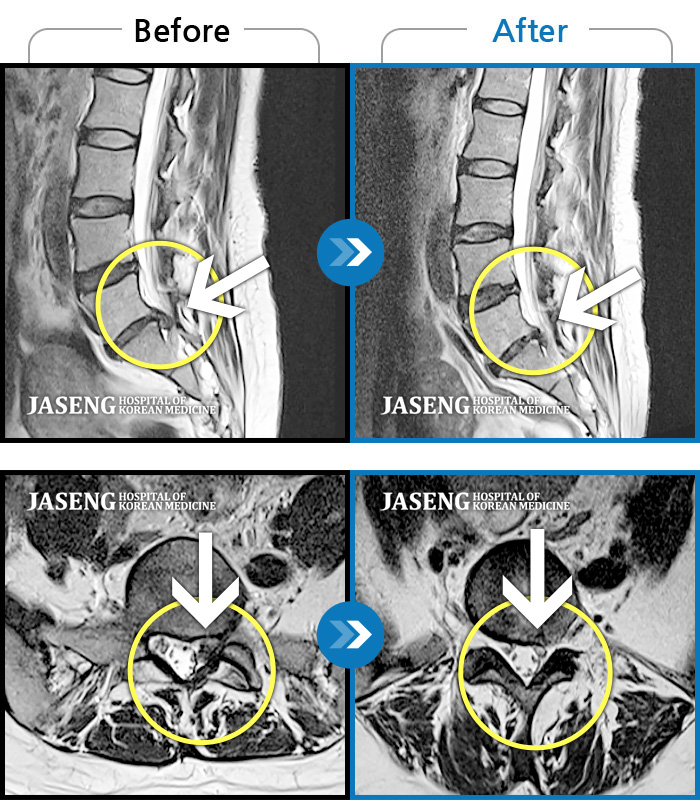

Before

After

환자에게 사전 동의를 받아 동일 조건에서 촬영되었습니다.

개인에 따라 치료 후 부작용이 발생할 수 있으니 의료진과 상담 후 치료를 진행하시기 바랍니다.

기침하면 허리 통증 발생, 몸을 비틀면 우측 허벅지에서 종아리까지 통증